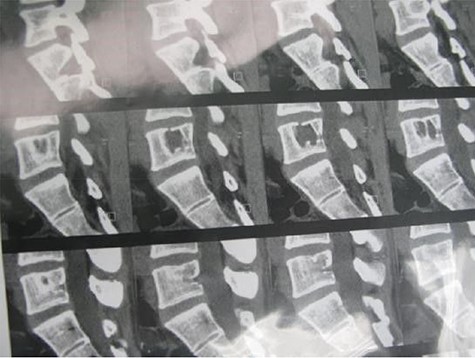

A 24-year-old male presented with acute low back pain with no prior traumatic events. Physical examination was unremarkable except for tenderness over the lower thoracic spine. The laboratory tests including complete blood count, renal function tests, alkaline phosphatase, aspartate aminotransferase, alanine aminotransferase, serum calcium, serum phosphorus and parathyroid hormone were all within normal limits. Initially, the patient was treated conservatively but the pain did not improve. Lumbar X-ray showed mild height loss and fracture of the superior endplate of T12 vertebra (Fig. 1). Computed tomography (CT) showed a multi-lobulated osteolytic lesion within the T12 body with extension to the right pedicle and transverse process (Fig. 2). Magnetic resonance imaging (MRI) revealed a well-defined lesion with low signal intensity on T1 and high signal intensity on T2 weighted images (Fig. 3). The bone scan showed a cold spot at the site of the lesion. The patient underwent surgery and excisional biopsy through the posterior approach. A large clear fluid-filled cavity was curetted and the cavity was filled with an autologous bone graft from iliac crest. Posterior spinal fusion was performed with instrumentation with pedicle screws from T10 to L2 and a mixture of autologous bone graft and allograft was used to achieve better fusion (Fig. 4). Pathology report confirmed the diagnosis of SBC and the patient received no further treatment (Fig. 5). The patient had no recurrence in 10-year follow up.